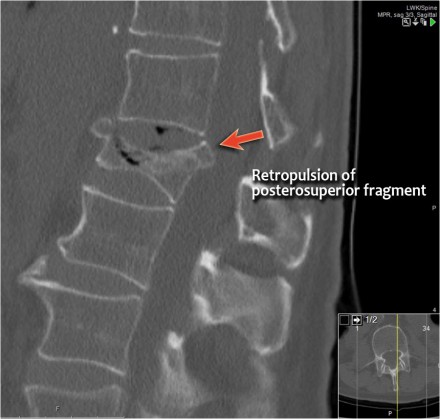

Retropulsion of posterosuperior vertebral body fragment

Retropulsion of a fragment is the typical feature of a burst fracture and distinguishes it clearly from a simple compression fracture.

- The morphology is of a vertebral fracture with retropulsion of a fragment, i.e. burst (2 points)

- The PLC is injured with edema of the interspinous ligament and a torn flaval ligament (3 points).

Based on imaging alone, the TLICS score is 5 points and this patient is a surgical candidate.